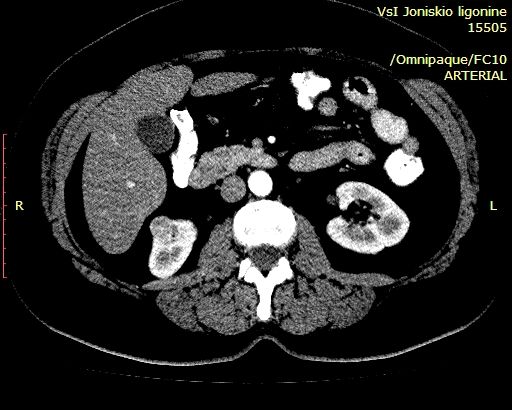

Женщина 55 лет, жалоб нет.

В нижнем полюсе правой почки обнаружено такое образование.

Немного похоже на AML, но неоднородное по структуре и с внутренним кровотоком, характеристики которого не в пользу RCC. Нет гипоэхогенного ободка, как при RCC.

Выполнена КТ с контрастированием.